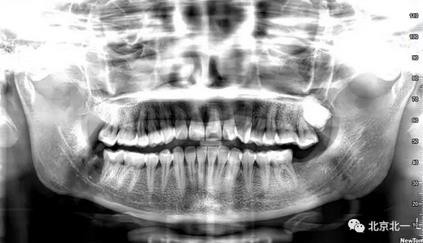

病例資料:一般情況,患者女性,28歲, 主訴:要求拔右側下頜智齒,檢查:右側下頜第三磨牙未見萌出, 拍片如圖。

圖一:CBCT顯示右側下頜水平骨埋伏牙,牙冠距離下牙槽神經管接近。